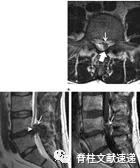

图注:64岁女性,硬膜内胸椎间盘突出症,表现为进行性胸背痛和脊髓损害症状。术中见椎间盘骨赘复合体与硬脑膜紧密粘连。病理组织学检查示椎间盘组织和纤维化伴局灶性炎症改变。